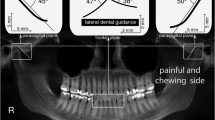

There was a non-significant trend in control subjects having a higher net maximum voluntary bite force (317.1 ± 206.6 N) than unilateral total TMJR patientswhen biting on their contralateral molars (249.6 ± 24.4 N) and their ipsilateral molars (164.2 ± 62.3 N) (Table 2). When biting on the contralateral molars, unilateral total TMJR patients had significantly higher bite force angle directed lingually than when biting on their ipsilateral molars (median difference: 7.3°, p = 0.048) (Fig. 4), which resulted in significantly higher lateral shear force directed lingually (median difference: 41.2 N, p = 0.048) (Table 2).

Net maximum voluntary bite force and direction for control subjects (blue) and unilateral total TMJR patients biting on their contralateral (yellow) or ipsilateral (pink) first molars. Bite force is reported as the reaction force on the mandibular teeth with respect to the mandibular anatomic coordinate system. The lateral component of bite force directed buccally is defined as positive, and that directed lingually is defined as negative. Statistically significant differences (p < 0.05) are identified by an asterisk